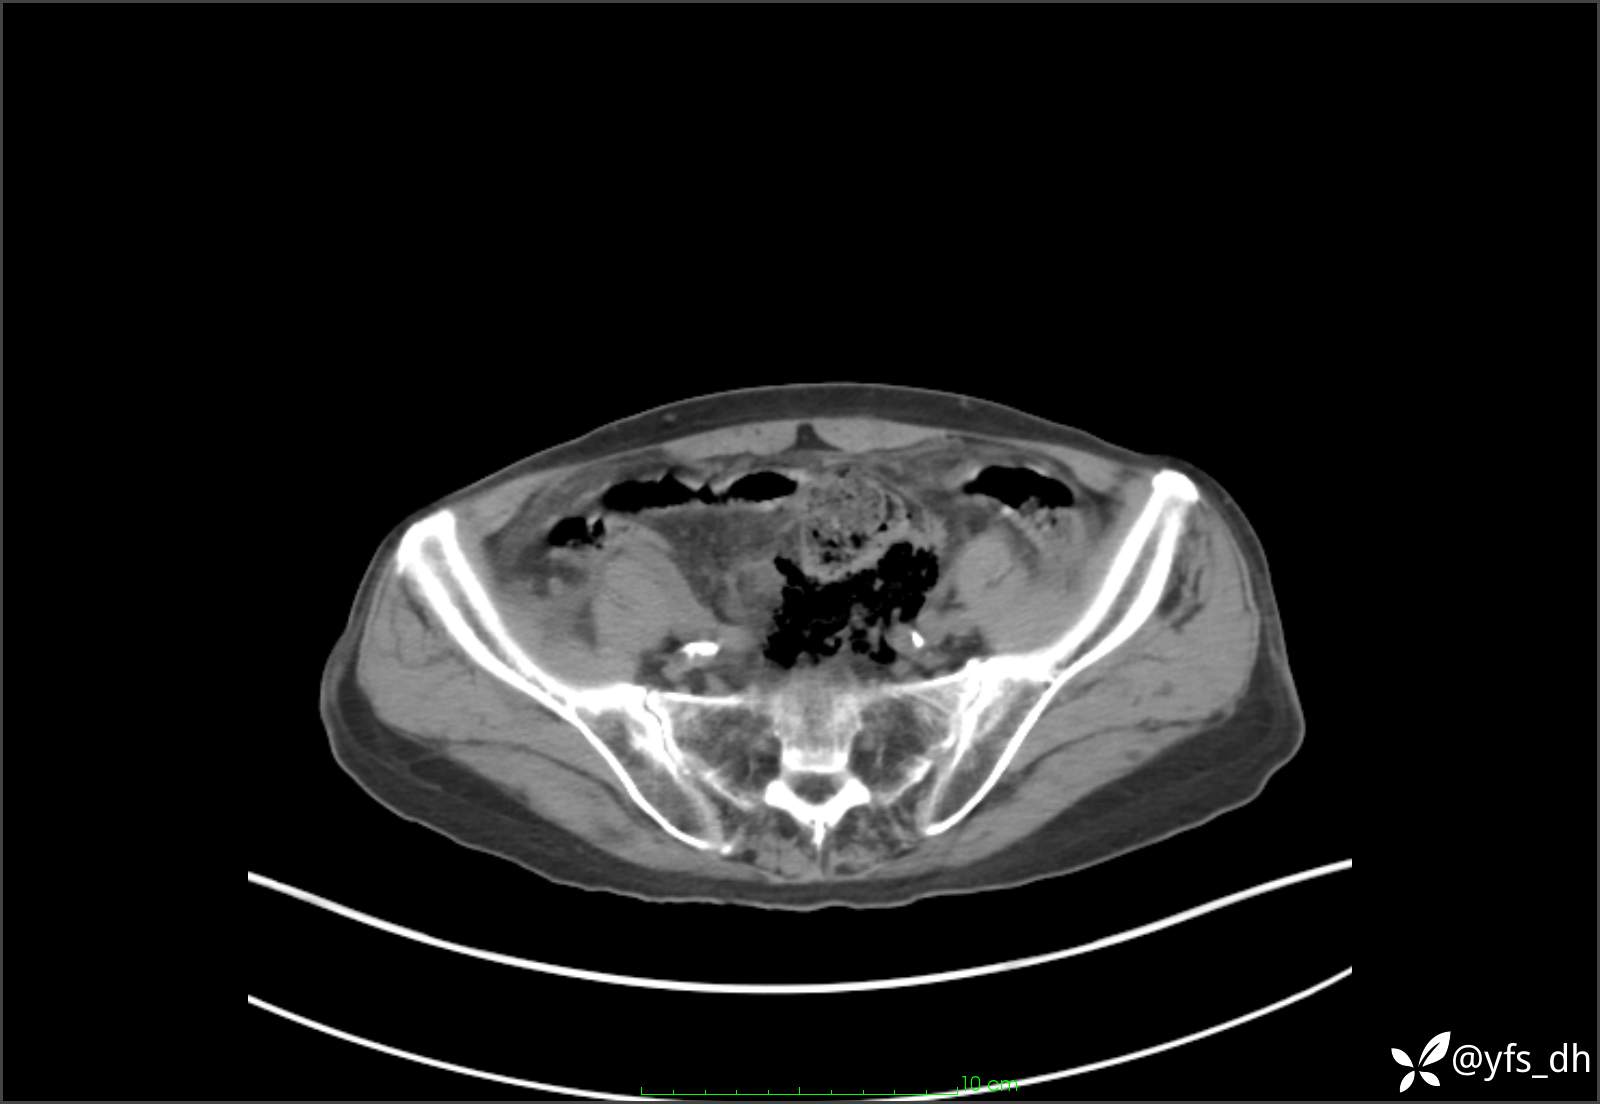

1.简要病史:患者4天前突发上腹部疼痛不适,但可以忍受。3小时前饭后突然加重,不能忍受后就诊。

2.简要手术记录:术中见腹盆腔大量肠液及粪便,乙状结肠中下段见一约3cm的破口。